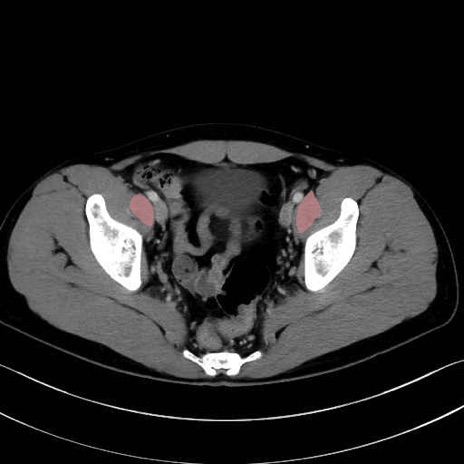

4. 深層外旋六筋(股関節の深部)

梨状筋 (Piriformis)

内閉鎖筋 (Obturator internus)

外閉鎖筋 (Obturator externus)

大腿方形筋 (Quadratus femoris)